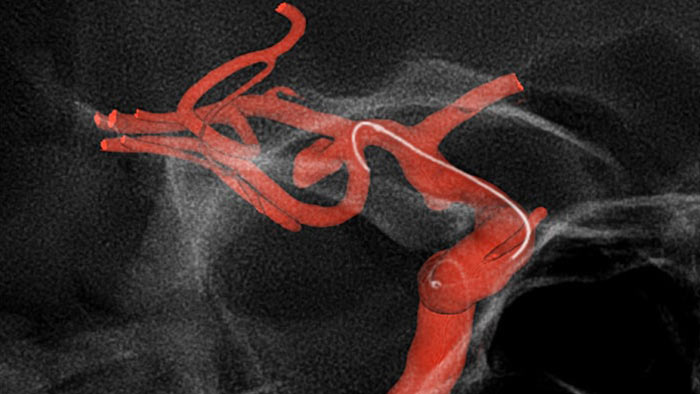

MR-CT Roadmap offers the possibility to overlay a previously acquired SmartCT Angio or MR angio scan with live fluoroscopy to visualize lesion boundaries and corresponding vascularization for risk assessment. Re-using pre-acquired data helps you manage X-ray dose and contrast medium.

SmartCT Roadmap facilitates complex interventions by providing live 3D image guidance that can be segmented, using SmartCT Angio or SmartCT Soft Tissue, to emphasize target vessel and lesions, aiding guidewire and catheter navigation through complex vessel structures. All controlled via the touch screen at the table.